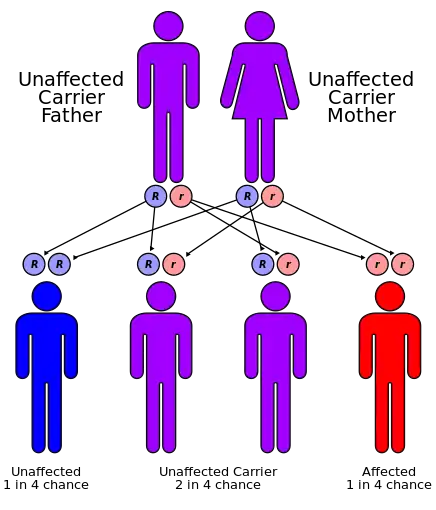

There is no permanent cure for this syndrome, although patients can be symptomatically treated. Treatment usually involves physical therapy and minor surgeries to the affected organs, such as cataract removal.[4] Also wearing high-factor sunscreen and protective clothing is recommended because Cockayne Syndrome patients are very sensitive to UV radiation.[20] Optimal nutrition can also help. Genetic counseling for the parents is recommended, as the disorder has a 25% chance of being passed to any future children, and prenatal testing is also a possibility.[4] Another important aspect is the prevention of recurrence of CS in other siblings. Identification of gene defects involved makes it possible to offer genetic counseling and antenatal diagnostic testing to the parents who already have one affected child.[21]